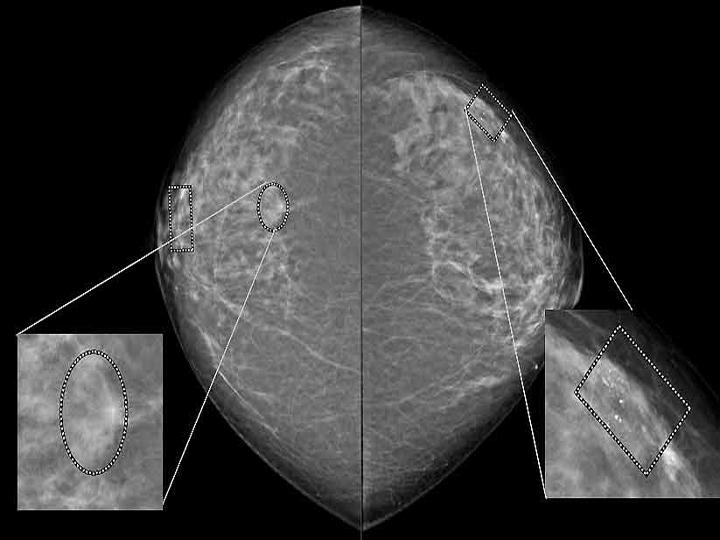

Whatever the individual situation, our innovations make screening and early diagnosis more reliable, efficient and comfortable than ever before - enabling early and therefore more effective therapeutic intervention.